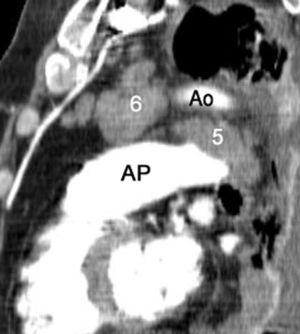

La precisión de la TC para predecir la afectación ganglionar mediastínica, pese a la ayuda que suponen las reconstrucciones MPR y 3D en la valoración de determinados territorios ganglionares (espacio subcarinal, hilio o ventana aortopulmonar) (fig. 11), sigue teniendo muchas limitaciones. El único criterio que se emplea para considerar que un ganglio es patológico es el tamaño (cuando el eje corto es mayor de 10 mm, salvo en el espacio subcarinal que se acepta hasta 12 mm). El empleo únicamente de criterios de tamaño hace que la TC sea una técnica poco precisa en la valoración de la afectación ganglionar. En un metaanálisis reciente13 la sensibilidad global de la TC para estadificar el mediastino fue de un 57%, con una especificidad del 82%, un valor predictivo positivo (VPP) del 56% y un valor predictivo negativo (VPN) del 83%. Lo que es innegable es la capacidad de la TC para mostrar un mapa de los ganglios tanto hiliares como mediastínicos (fig. 12), lo cual es de gran utilidad en la determinación del factor N. La valoración del territorio hiliar puede ser compleja por la agrupación de estructuras vasculares, por lo que además de la opacificación adecuada de éstas, es de utilidad la identificación de la pérdida del ángulo de la bifurcación (carina secundaria), ya que el eje corto significativo en este territorio es de 3 mm. Como ya hemos comentado, también es de gran ayuda en esta localización el empleo de reconstrucciones (fig. 11)5.

Fig. 11.--N2. (A) Corte axial de tomografía computarizada (TC) con contraste. Nódulo heterogéneo en el segmento 6 del lóbulo inferior derecho con infiltración de la vena pulmonar inferior (flecha). (B) En la reconstrucción de volumen se ponen de manifiesto la infiltración tumoral de la vena pulmonar (flecha negra), la adenopatía hiliar (asterisco) y una adenopatía calcificada lobar superior derecha (flecha blanca).

Fig. 12.--Estaciones ganglionares para la estadificación del cáncer de pulmón. Las reconstrucciones multiplanares (MPR) son de gran ayuda para precisar los territorios ganglionares afectos. Correlación de los territorios ganglionares entre el mapa ganglionar de Mountain y Dressler y una reconstrucción coronal de un paciente con afectación adenopática mediastínica e hiliar bilateral. (A y B) Ganglios mediastínicos superiores e inferiores e hiliares. (C y D) Ganglios aórticos. AP: arteria pulmonar. Ao: aorta.